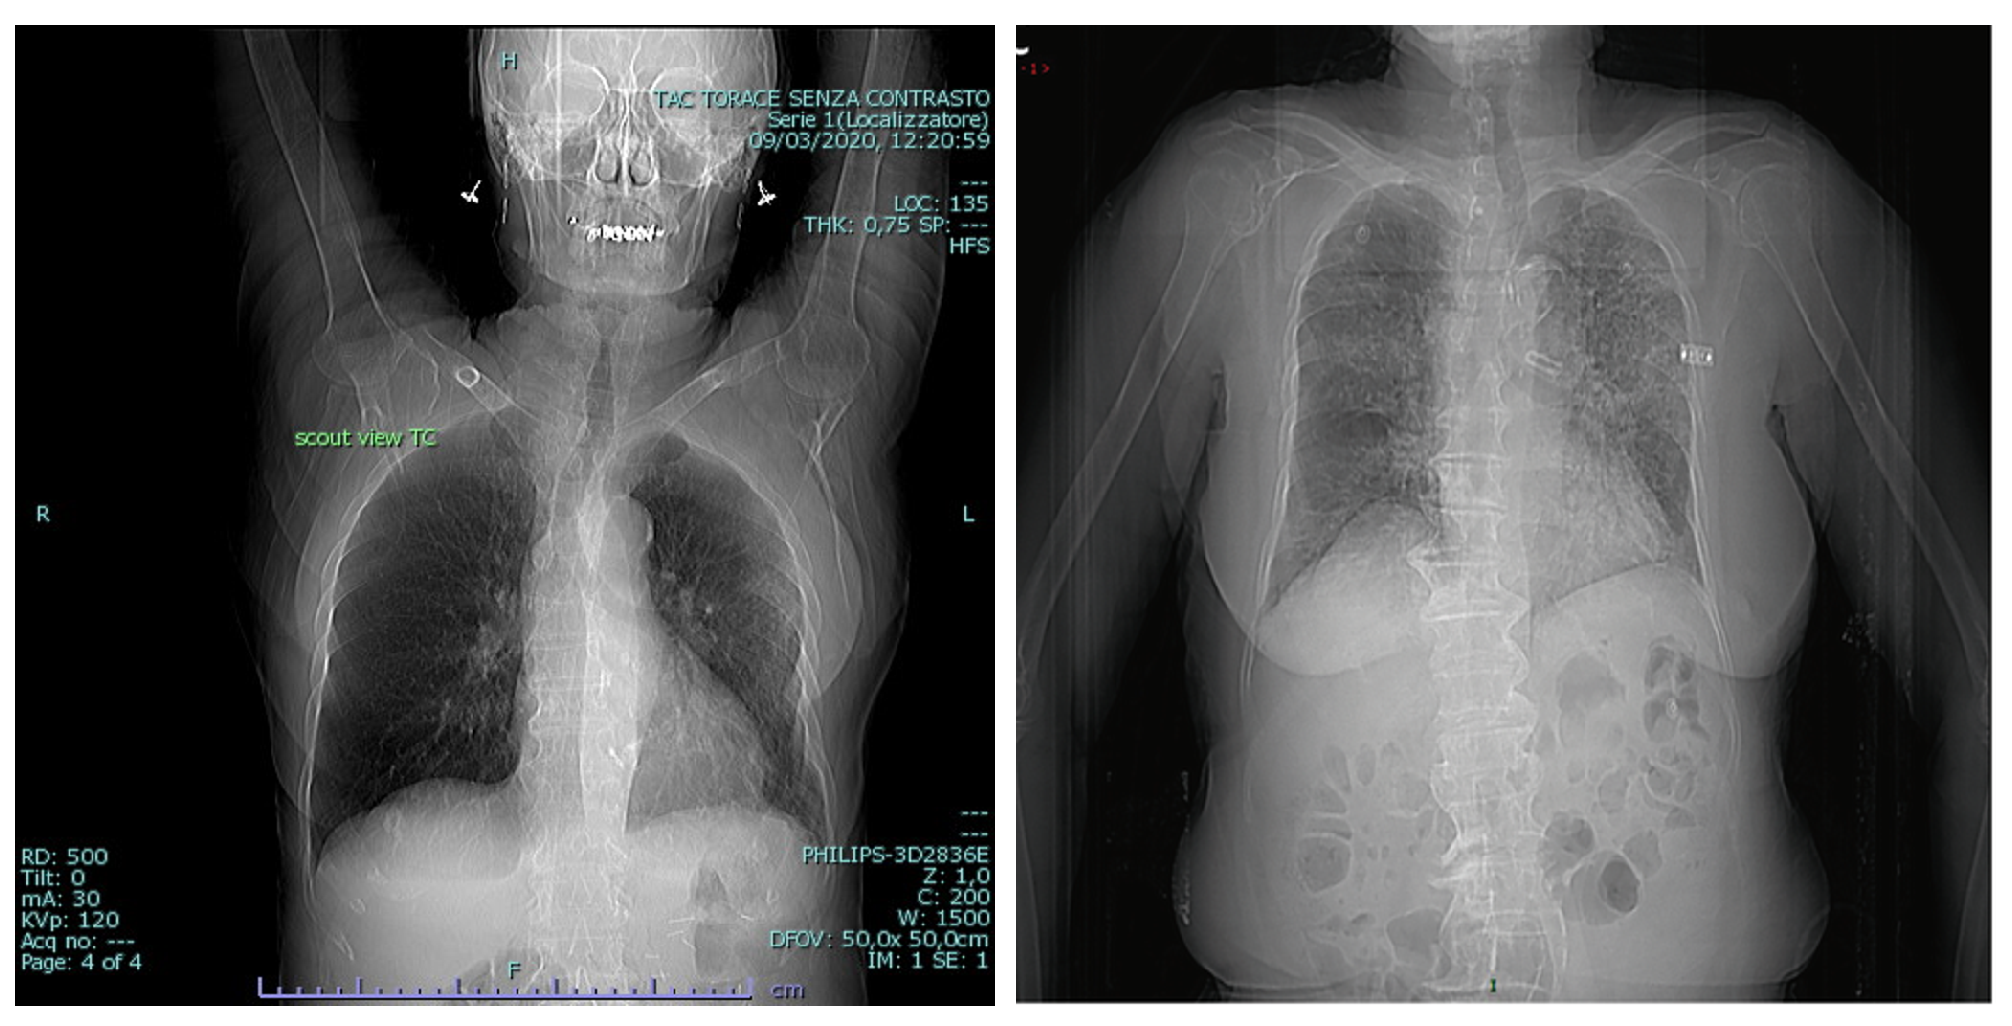

3.3. BIMCV COVID19+